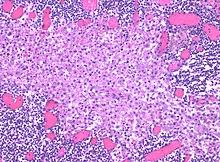

In medicine, histiocytosis is an excessive number of histiocytes[1] (tissue macrophages), and the term is also often used to refer to a group of rare diseases which share this sign as a characteristic. Occasionally and confusingly, the term "histiocytosis" is sometimes used to refer to individual diseases.

Sinus histiocytosis, a common feature in lymph node biopsies, is characterized by dilated sinuses containing variable numbers of histiocytes.[6]